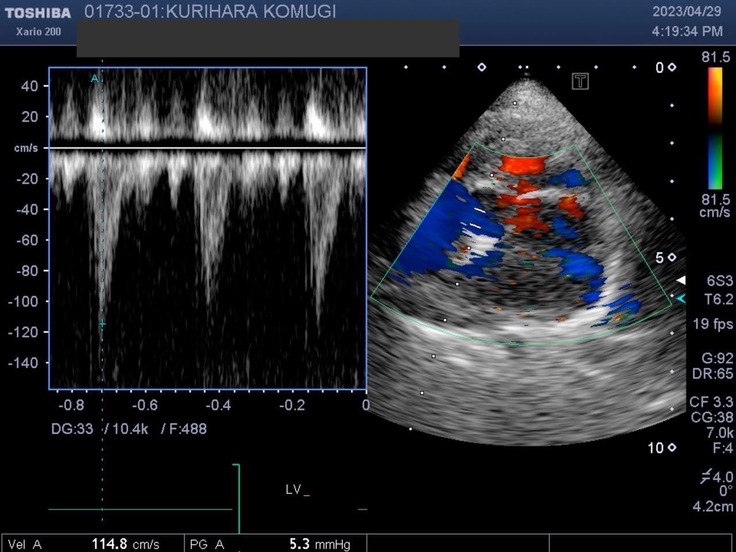

▽エコー写真

※かかりつけの動物病院からの掲載許可をいただいています。

一週間〜二週間に一度のペースでレントゲン撮影やエコー検査、血液検査をしています。

※循環器専門病院からの掲載許可をいただいています